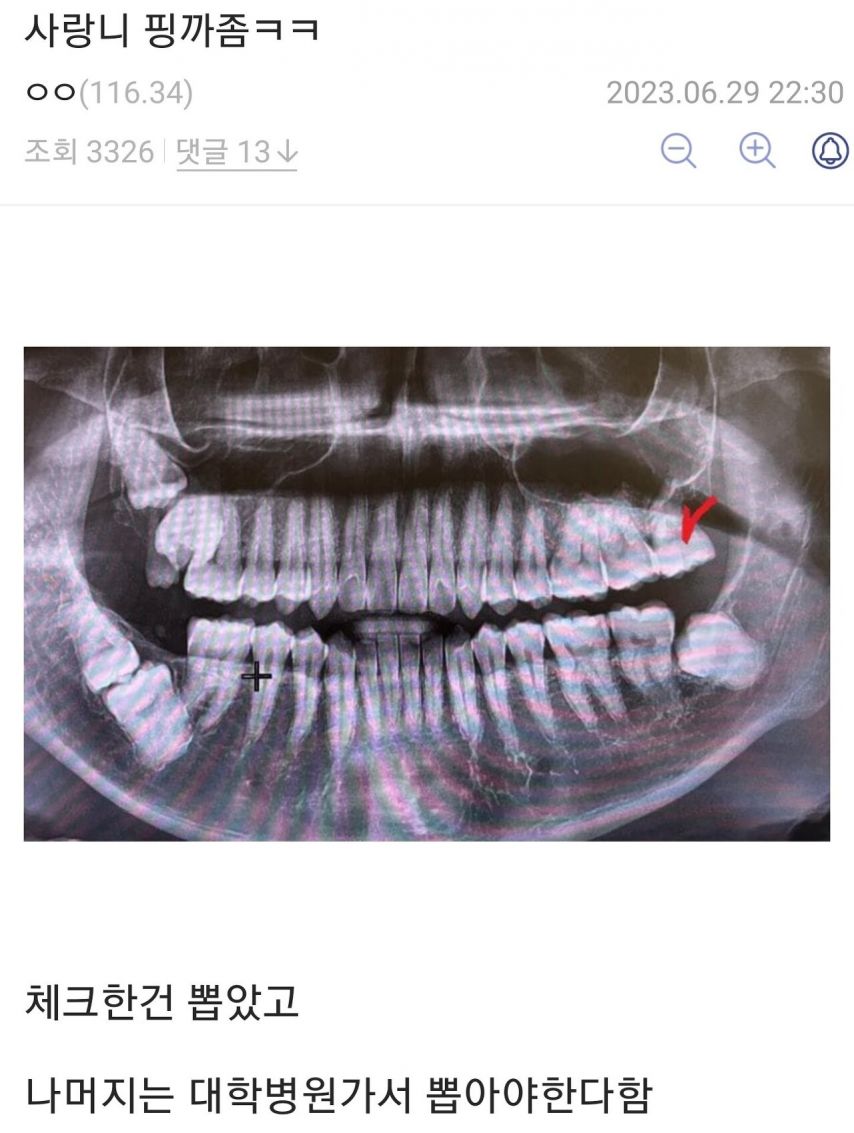

사랑니 평가